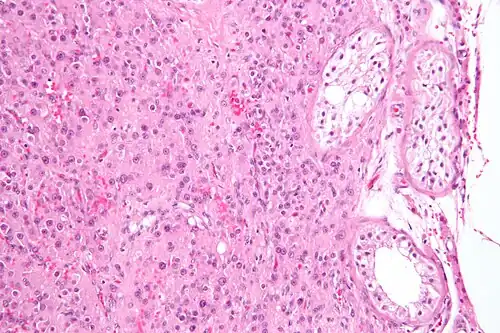

| Micrograph of a Sertoli cell tumour. H&E stain. | |

A Sertoli cell tumour, also Sertoli cell tumor (US spelling), is a sex cord–gonadal stromal tumour of Sertoli cells. They can occur in the testis or ovary. They are very rare and generally peak between the ages of 35 and 50. They are typically well-differentiated and may be misdiagnosed as seminomas as they often appear very similar.[1]

Microscopy and immunohistochemistry are the only way to give a definitive diagnosis, especially when there is a suspected seminoma.[3]